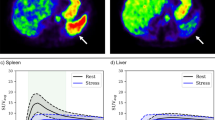

To quantitatively assess SSO in PET, the activity values in the stress and rest datasets were converted into standardized uptake values (SUV) using the administered tracer dose, tracer half-life and time of administration and recorded using commercially available software (PMOD Software Package Version 3.805, PMOD Technologies LLC, Zürich, Switzerland). Volumes of interest were placed in the spleen (10-mm radius sphere) and liver (20-mm radius sphere) to generate time–activity curves from the dynamic PET datasets. The splenic activity ratio (SAR) was calculated as the peak splenic activity during stress over the peak splenic activity at rest (SAR = splenic activityStress/splenic activityRest), (Figure 2). The spleen-to-liver activity ratio during stress (SLRStress) was calculated by dividing the peak splenic activity during stress by the peak liver activity during stress (SLRStress = splenic activityStress/liver activityStress). Similarly, the spleen-to-liver activity ratio during rest (SLRRest) was calculated by dividing the peak splenic activity during rest by the peak liver activity during rest (SLRRest = splenic activityRest/liver activityRest). The stress-to-rest spleen-to-liver activity ratio (SLRStress/Rest) was calculated by dividing the SLRStress by SLRRest (SLRStress/Rest = SLRStress/SLRRest). Quantitative myocardial blood flow (MBF) was obtained from stress and rest PET scans, and global MFR was calculated as the ratio of stress over rest MBF using commercially available software (CSI 2017.7 Cedars-Sinai Medical Center, Los Angeles, CA, USA). An MFR < 1.7 was defined as impaired flow reserve.12

Nitrogen-13 ammonia PET in a patient undergoing adenosine stress PET/MR. A transaxial slice through the spleen is shown. There is lower tracer activity of the spleen (*) during stress (A) as compared to rest (B). Similarly, a quantitative assessment by splenic time activity curves, showing a SAR of 0.29 (positive SAR) (C)

SLRStress was significantly lower than SLRRest (0.75 [IQR 0.55 to 1.15] vs. 2.05 [IQR 1.7 to 2.36]; P < .001). SLRRest did not differ significantly between patients with positive versus negative SSO (2.05 [± 0.49] vs. 2.12 [± 0.55]; P = .666; Figure 5a). SLRStress was significantly lower in patients with positive versus negative SSO (0.68 [IQR 0.51 to 0.91] vs. 1.5 [IQR 0.98 to 1.83]; P < .001; Figure 5b). ROC analysis for SLRStress to detect positive SSO showed an area under the curve of 0.83 and a cut-off value of 0.92 (Figure 5c). Using this threshold, a sensitivity of 78%, specificity of 85%, PPV of 94% and NPV of 58% were calculated. SSO and SLRStress < 0.92 showed moderate agreement (κ = 0.55, P < .001).